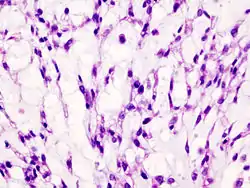

Histopathology

Imaging studies - including radiographs ("x-rays"), computerized tomography (CT), and magnetic resonance imaging (MRI) - are often used to make a presumptive diagnosis of chondrosarcoma.[11] However, a definitive diagnosis depends on the identification of malignant cancer cells producing cartilage in a biopsy specimen that has been examined by a pathologist. In a few cases, usually of highly anaplastic tumors, immunohistochemistry (IHC) is required.

There are no blood tests currently available to enable an oncologist to render a diagnosis of chondrosarcoma. The most characteristic imaging findings are usually obtained with CT.